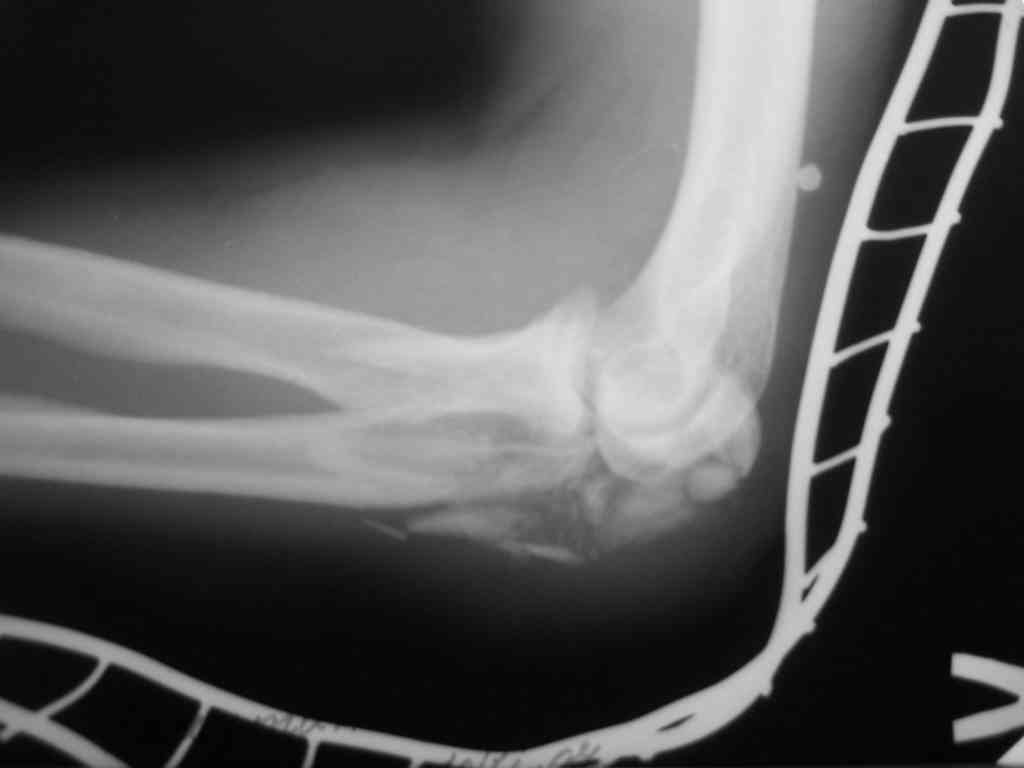

Уважаемый Владимир! Судя по представленному снимку перелом многооскольчатый, но снимок сделан в транспортной иммобилизации видимо при поступлении. Необходимы снимки в стандартных проекциях, чтобы можно было, что-нибудь посоветовать. При данном переломе главное попытаться восстоновить суставную поверхность локтевой кости, поэтому я бы посоветовал идти стандартным путем, разрез Z- образный, крупные отломки фиксировать спицами и если получится стягивающей проволочной петлей, под которую уложить мелкие отломки. Своего мнения не навязываю.

Снимки вот еще какие есть (наши лаборанты пытались сделать что то)

Good day dears colleagues! You presentated only one x-ray proection - lateral- of elbow.Accorden this I thing that this isn't avulsion fracture of olecranon,as usually can to see.This is Monteggia like fracture with subluxation of radial head.If

you can show AP x-ray or more more better CT elbow

I will more sure.Any way more imported of all normal long of ulna.So my recomendation ORIF proximal ulna by LCP - allow normal long by bridging, without attention to continues cortex but attention to articular surfase. On operation examen of radial head,becouse my sence isn't without damage.Operation by standart approach.